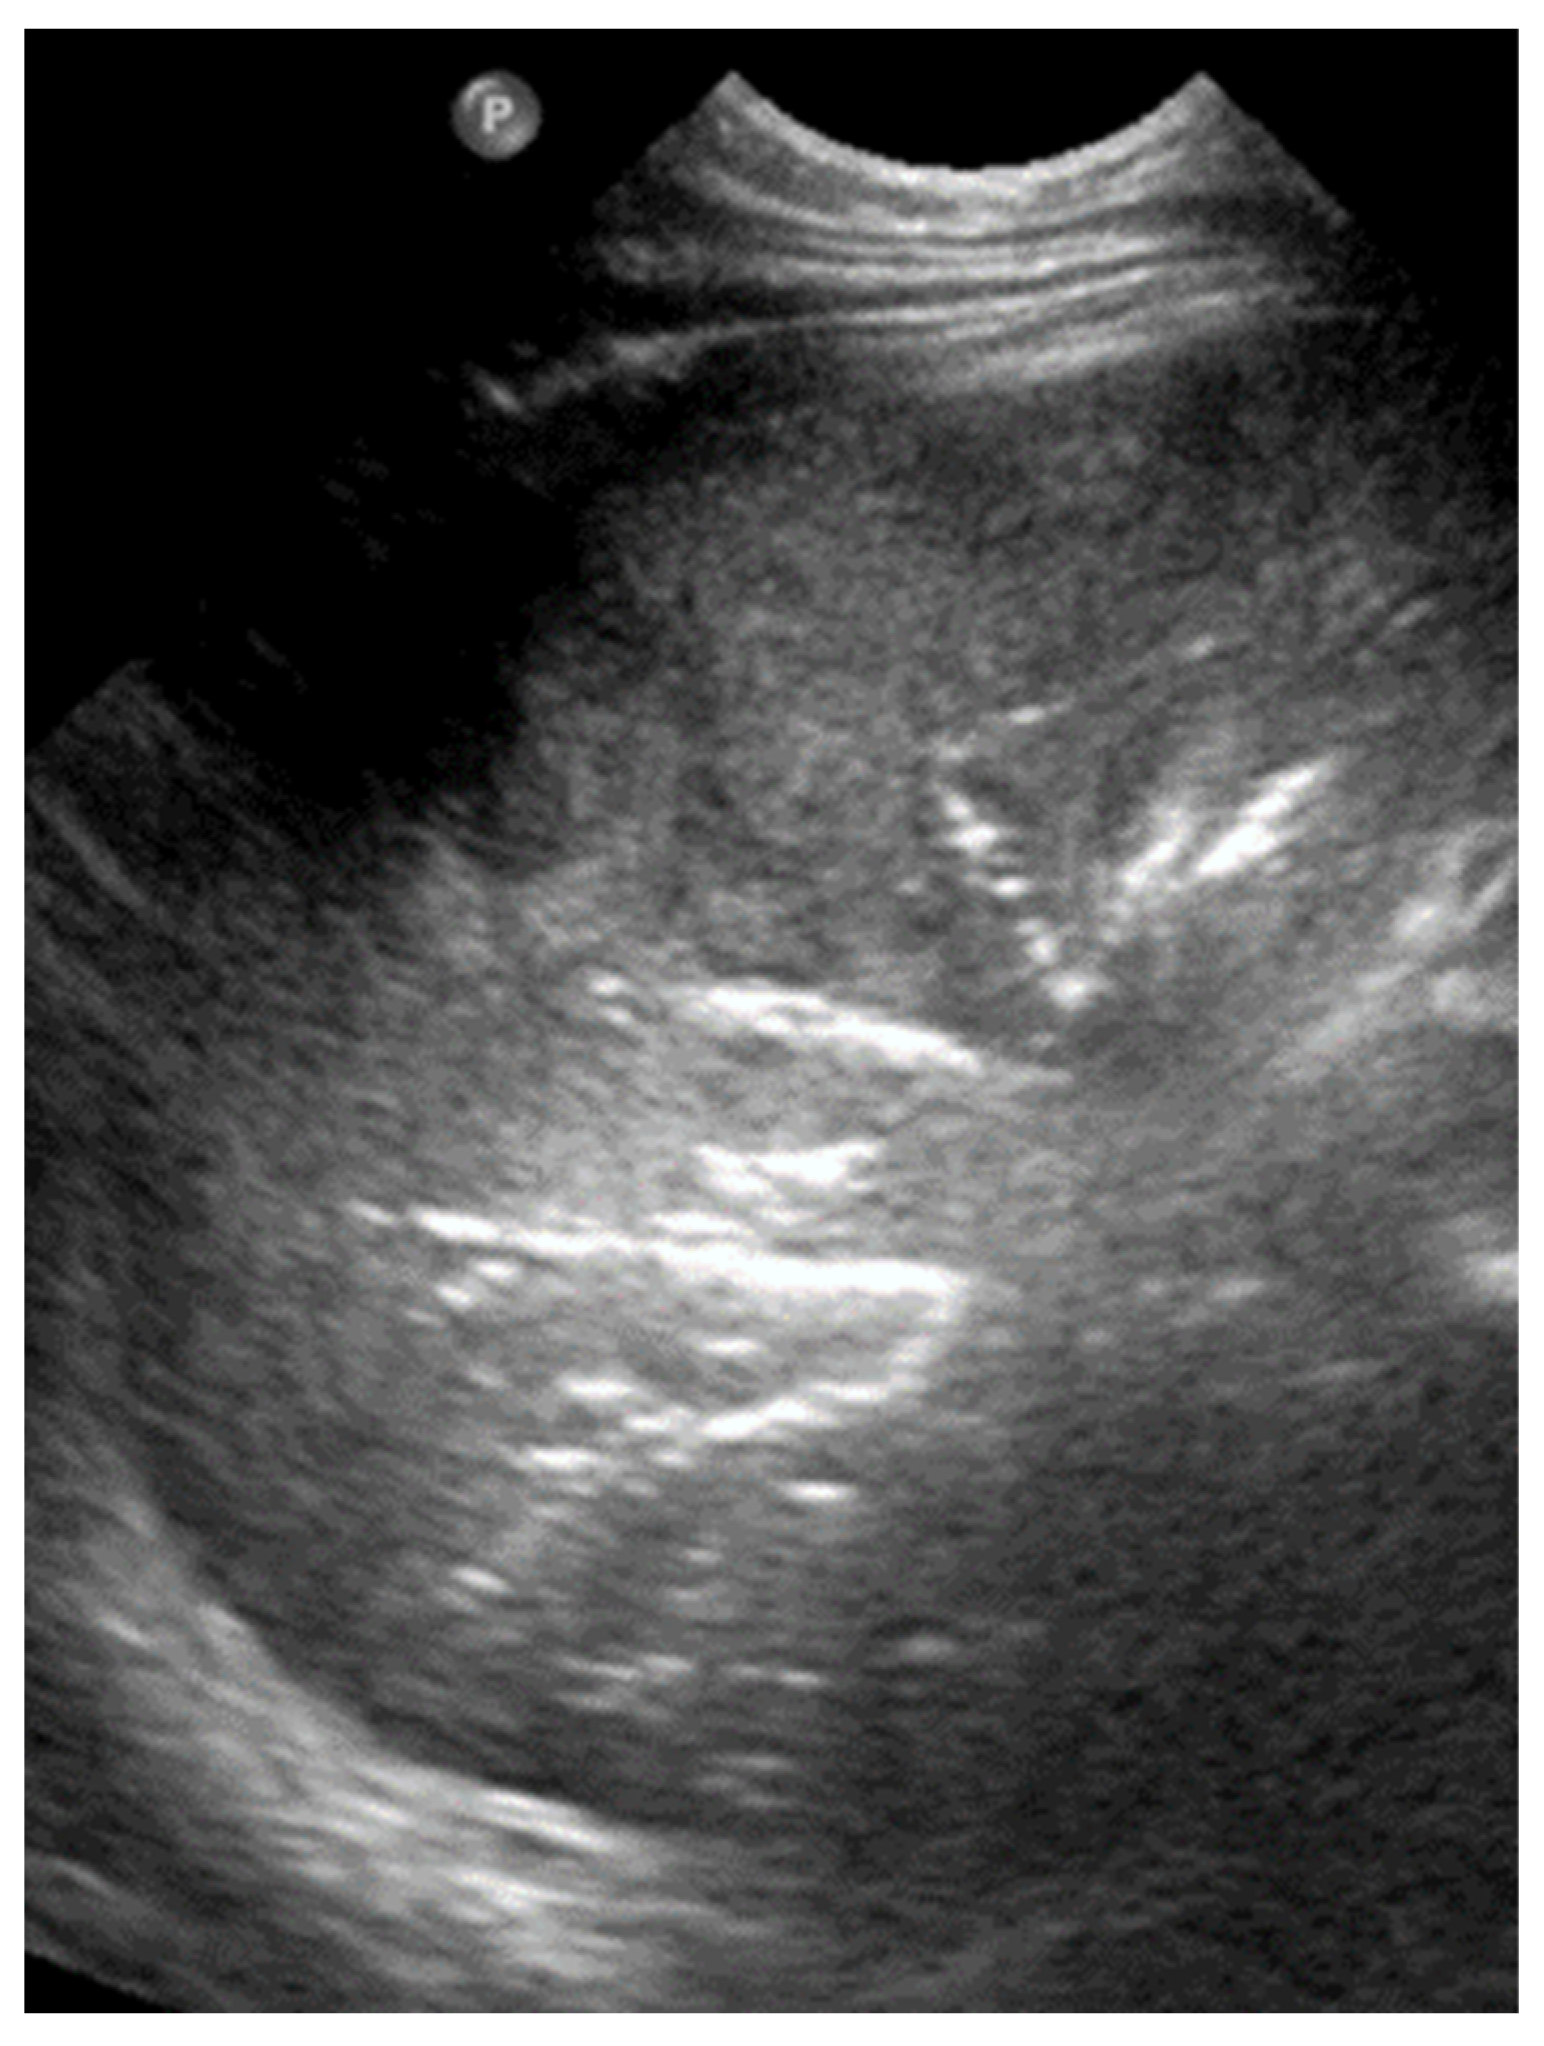

3.2.7. Lung Consolidation

In LUS, pulmonary consolidation refers to the replacement of normally aerated lung tissue with fluid, cells, or other pathological material, leading to a loss of the usual air-filled ultrasound pattern. The characteristic LUS signs of alveolar pathology, such as pneumonia, include the absence of the pleural line, the presence of air bronchograms, and hepatization of the lung parenchyma due to alveolar filling with exudates or pus (Figure 20).

Figure 20.

Lung consolidation (alveolar filling with exudate/pus): hepatization of lung parenchyma containing air bronchogram (normal branching pattern of the air-filled bronchi).

Pneumonia is also identified by the appearance of an irregular echogenic artifact, known as the “shred sign”, which is created by the inhomogeneous interface between consolidated (non-ventilated) and aerated lung tissue (Figure 21) [12,13,20,26,51].

Figure 21.

Shred sign: (a) CXR: lung consolidation in right upper lobe; (b) LUS: area with irregular margins and heterogeneous echogenicity.

One of the most distinctive sonographic features of consolidation is the hepatization of the subpleural lung tissue, where the affected area appears with an echotexture similar to liver tissue. This occurs due to the dense accumulation of inflammatory exudates within the alveoli, causing the lung to become uniformly solid in appearance. The consolidated lung often extends to the pleural surface and may exhibit associated signs, such as dynamic air bronchograms. The presence of a dynamic air bronchogram in LUS is a sign that helps distinguish pneumonia from other conditions such as atelectasis. It refers to air-filled bronchioles (airways) that move synchronously with respiration, indicating that they are open and connected to larger airways [31,52]. This movement contrasts static air bronchograms, which remain fixed, and suggests that the airways are obstructed. In addition, it presents with other signs, such as irregular pleural lines and pleural effusion. In neonates, lung consolidation is most seen in cases of pneumonia, atelectasis, or severe respiratory distress syndrome, and its identification is crucial for guiding appropriate management and follow-up care [12,20].